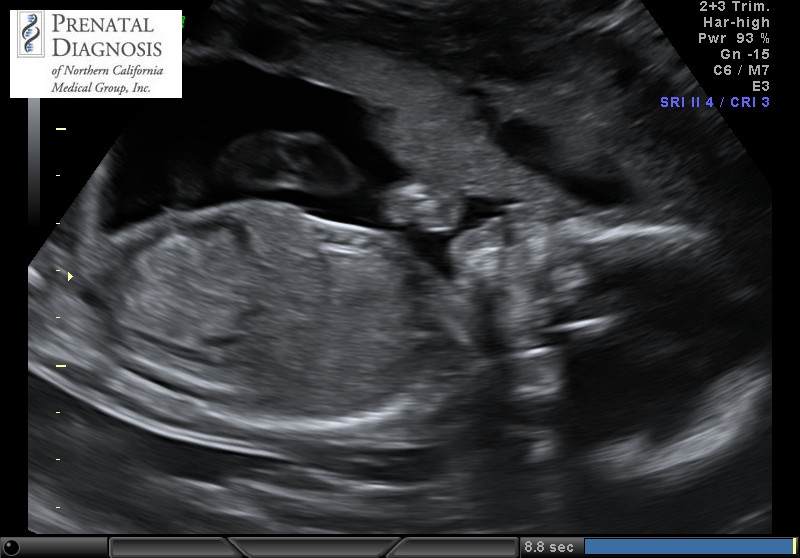

Had my anatomy scan today. She's measuring a little on the small side, 9 oz at 19w 5 d, which they said is in the 12th percentile, but otherwise she's doing great!